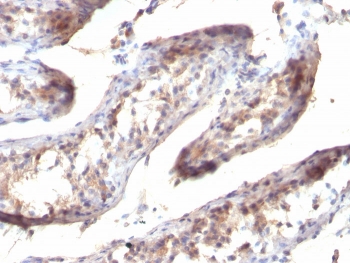

This antibody reacts with the C-terminus of TGF alpha and shows no cross-reaction with EGF and the neuropeptide synenkephalin. TGF-a is a growth factor with 33% homology to EGF, binds to EGFR, activates tyrosine phosphorylation of the receptor, and stimulates cell proliferation. It plays a role in tumor initiation by inducing the reversible transformed phenotype.

A 17-amino acid peptide from the C-terminus of the rat protein was used as the immunogen for this TGF a antibody.